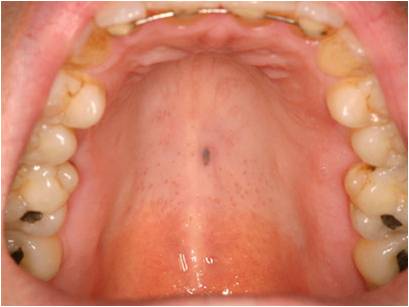

口腔黑色素瘤早期症状图片

图片尺寸625x600